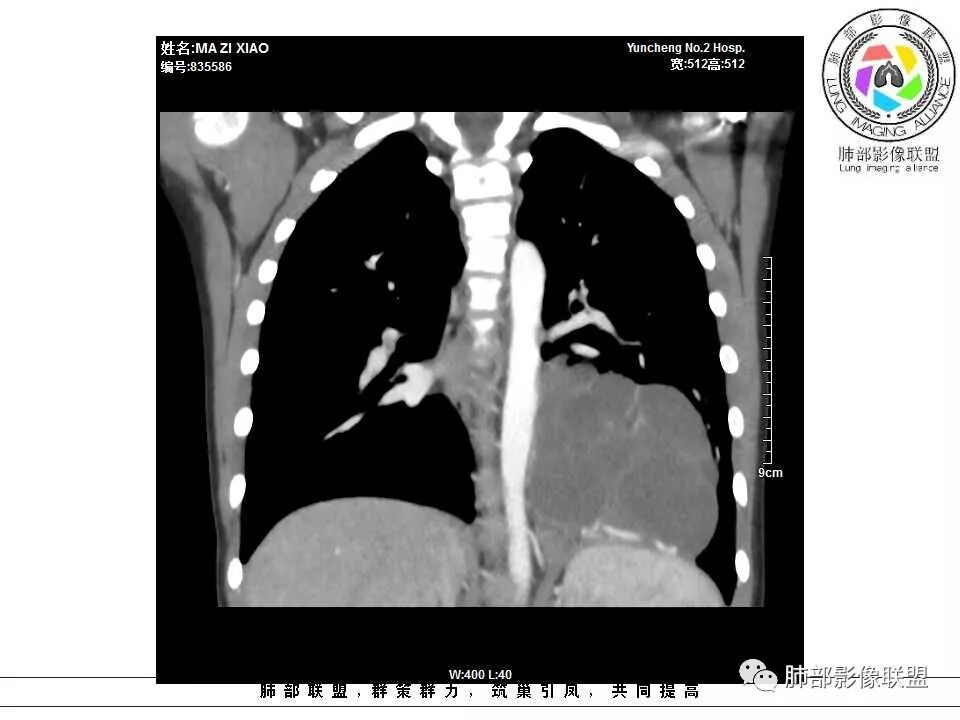

病例提供:运城市第二医院  王崇军

肺隔离症,供血动脉来源腹主动脉

肺隔离症 膈下腹主动脉供血 肺静脉引流 多房改变支气管扩张积液?

左下肺囊性占位,多发分隔,增强分隔及边缘强化,腹主动脉供血,考虑肺隔离征。

儿童左下肺囊性占位,多发分隔,增强分隔可见强化,腹主动脉供血,肺隔离征。

左肺下叶病灶,囊性为主,内见分隔,边界清晰,首先考虑良性病变,增强可见体循环供血,考虑肺隔离症

儿童,左下病变,边界清,囊性,分隔明显,体循环供血,肺隔离症。

左下肺囊性变,内有分隔,体循环供血,支持隔离症。

病灶位于左肺下叶,边界清,囊性,内见分隔,增强可见体循环供血,支持肺隔离症。

左下肺囊性团块灶,多发分隔,增强分隔及边缘强化,主动脉供血,考虑肺隔离症,叶外型。

左下肺囊状影,内有分隔,体循环供血(腹主动脉),肺静脉回流,考虑隔离症

左肺下叶多房囊性病灶,主动脉分支供血,肺静脉回流,符合肺段隔离症,应该是肺外型吧

左肺下叶囊性占位,腹主动脉供血,肺动脉引流,考虑肺隔离症。

左肺下叶囊性变,可见多发分隔,增强后分隔及边缘可见强化,并可见降主动脉分支进入,考虑叶外型肺隔离症

左下肺肿块,内部见多分隔,囊性密度,增强见腹主动脉分支、肺动脉供血,考虑肺隔离症,鉴别支气管囊肿

儿童,左下肺多房囊性占位,增强分隔强化,腹主动脉供血,肺隔离征。

11岁男患,左肺下叶见囊性病变,期内见分隔,增强扫描见强化,供血血管清晰,考虑肺隔离症,不除外多房性囊性病变。

男,11岁,左肺下叶囊性包块,形态不规则,内有分隔,包膜及分隔明显强化,主动脉供血,肺静脉引流,基底段支气管显示不清,首先考虑常见病肺隔离症,支气管囊肿不排除

电话随访,患者在西安某医院手术,为肺隔离症,供血两支动脉,均来自腹主动脉,引流入肺静脉。